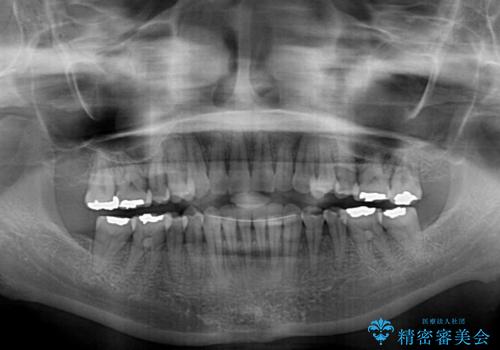

- 歯列不正と、どこで咬んで良いのか分からない咬み合わせを気にして来院された患者様です。

下顎骨は左側にシフトしており、咬み合ったときには奥歯と前歯の一部しか接触していない状態でした。

骨格的な左右差は歯列矯正は改善できないため、上下歯列が全体的に接触することをゴールとしてインビザラインにて矯正治療を行うこととしました。